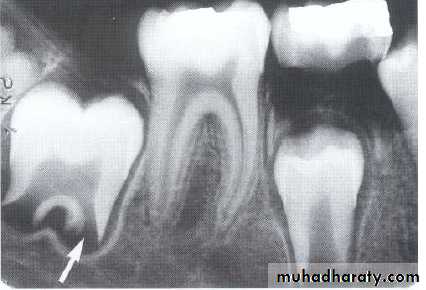

Radiograph of buccal or lingual caries. Buccal or lingual caries on this mandibular second premolar appears as a round radiolucency (superimposed over the pulp chamber)